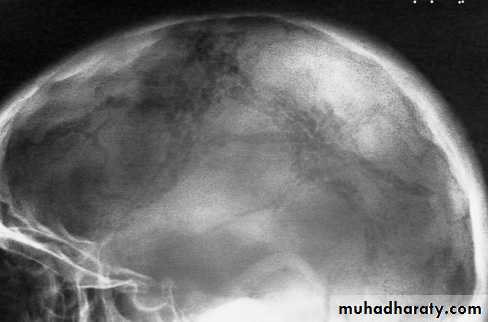

Langerhans histiocytosis